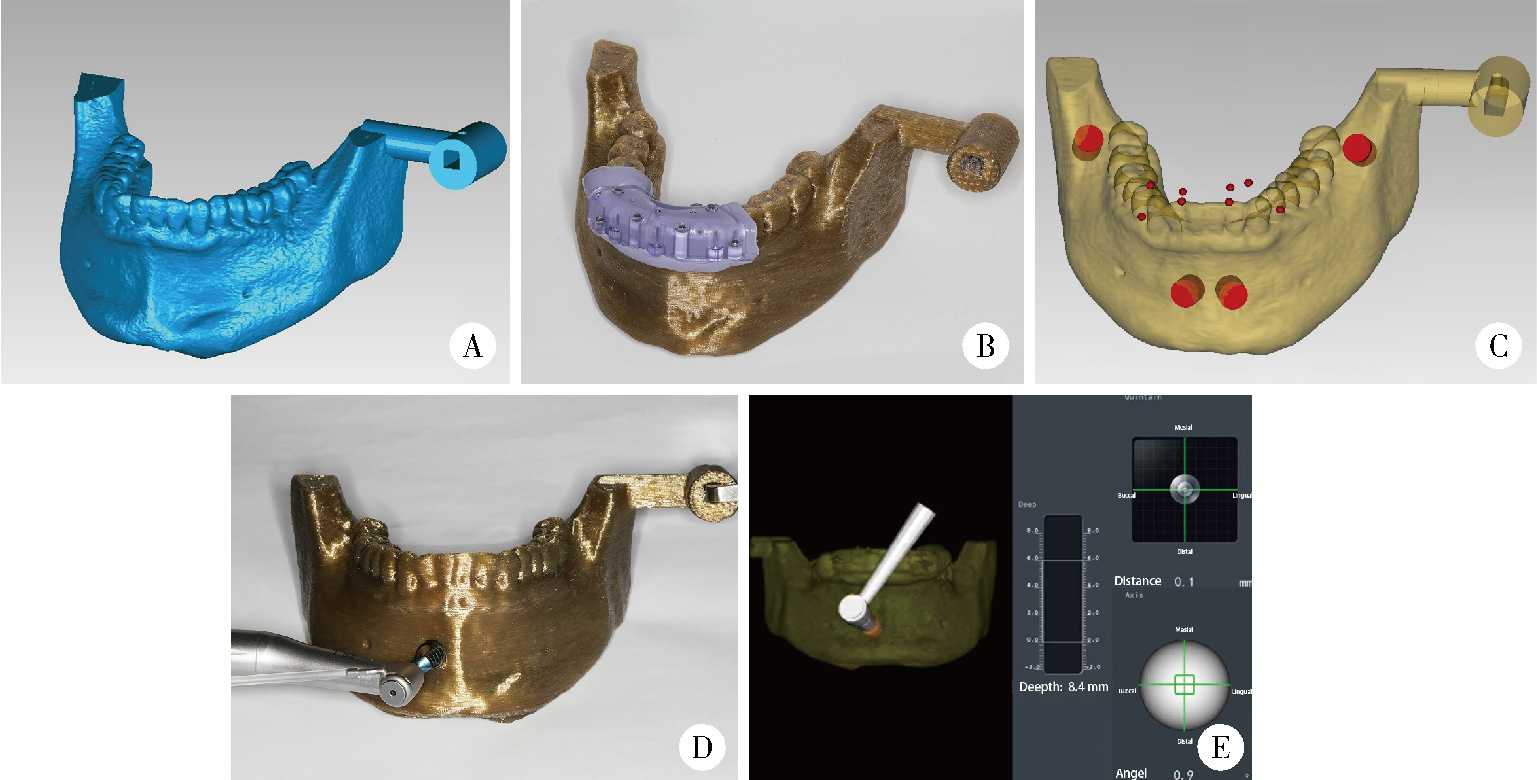

Accuracy of dynamic navigation-assisted trephine method for bone harvesting

Jiayu LIU, Ning ZHU, Yuchen CHANG, Xianming GAO, Yu ZHANG*( )

- Department of Oral Implantology, Peking University School and Hospital of Stomatology & National Center for Stomatology & National Clinical Research Center for Oral Diseases & National Engineering Research Center of Oral Biomaterials and Digital Medical Devices & Beijing Key Laboratory of Digital Stomatology, Beijing 100081, China